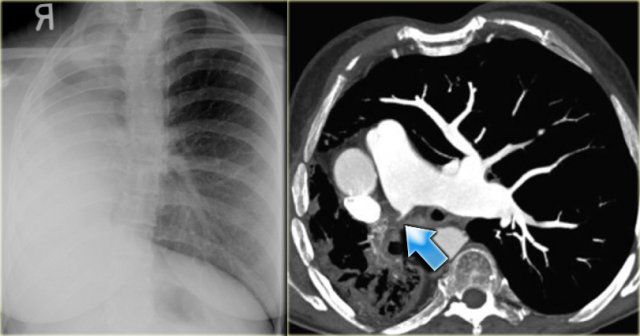

On the left a chest film of a 6-month old boy with stridor and cough.

The trachea is deviated to the left, otherwise the chest film is normal.

So there is some mass effect on the right side.

On the left the reconstructions demonstrating a double aortic arch.

There are branches coming off the right arch and branches coming off the left arch.

Double Aortic Arch Double Aortic Arch

The right arch is typically larger and higher than the left.

There is a complete ring that encircles the esophagus and the trachea and usually there is stridor or dysphagia.

Two brachiocephalic arteries arise on each side separately (four vessel sign).

On the left a chest film of a young adult with a cough.

There is a right paratracheal mass.

The differential diagnosis is tumor, adenopathy or vessel (right arch, dilated azygos vein, dilated aberrant right subclavian artery).

On the left axial images and posterior view of volume rendered reconstruction.

Describe the findings and then continue.

The findings are:

1. four vessel sign

2. double arch

3. right arch higher and larger

4. esophagus and trachea are completely encircled

The narrowing of the trachea is seen on the axial images, but better appreciated on the MPR and Volume Rendered image.